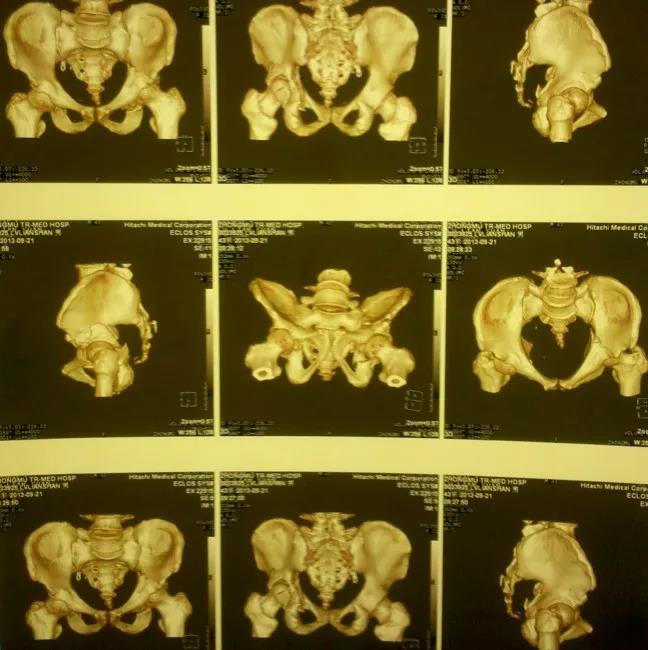

——髋臼骨折CT检查重要性——

1、显示常规X线不能显示的骨折,有助于诊断;2、可以清楚的显示关节内的碎骨块;3、显示关节面压缩、程度;4、精确显示骨折移位程度;5、定量显示后壁缺损情况;6、有助于术后分析。

——典型案例——

微创插板病历后路有限切开,结合前路微创插板内